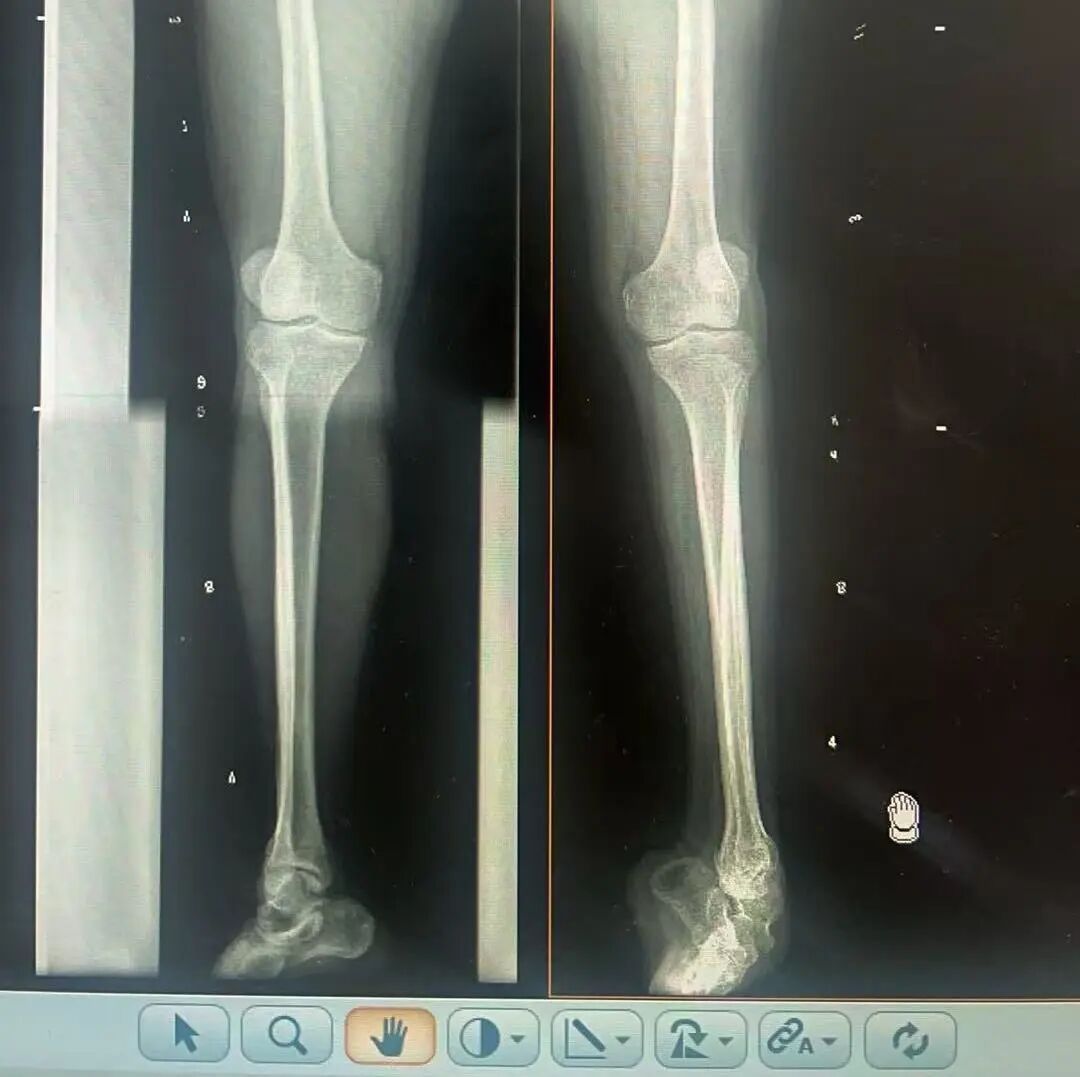

術(shù)前X光片 VS 術(shù)后治療效果

三十八年前,一紙“脊髓灰質(zhì)炎”的診斷,讓陽(yáng)先生的人生染上了陰霾。闖過(guò)了急性期的鬼門關(guān),但后遺癥——嚴(yán)重的左踝馬蹄內(nèi)翻足畸形,是一道無(wú)形的枷鎖,禁錮著他的成長(zhǎng)與自由。骨盆傾斜、雙腿不等長(zhǎng)、左腳嚴(yán)重內(nèi)翻,他成長(zhǎng)成人中行走的每一步,都伴隨著難以言說(shuō)的艱辛。

骨科隨即為陽(yáng)先生進(jìn)行了全面的檢查。診斷明確而復(fù)雜:陽(yáng)先生患有脊髓灰質(zhì)炎后遺癥、左踝馬蹄內(nèi)翻足、骨盆傾斜……面對(duì)這張沉甸甸的診斷書,由肢體功能重建顯微修復(fù)學(xué)科組長(zhǎng)鄭群龍所帶領(lǐng)的醫(yī)療團(tuán)隊(duì)沒有畏懼,“這是一個(gè)家庭38年的堅(jiān)守與期盼,我們必須全力以赴”

針對(duì)陽(yáng)先生的復(fù)雜情況,鄭群龍醫(yī)師團(tuán)隊(duì)制定了詳盡的手術(shù)方案:左踝關(guān)節(jié)融合+馬蹄足畸形矯正+跟腱延長(zhǎng)+外固定架固定術(shù)。手術(shù)的核心,正是伊里扎洛夫技術(shù)。這項(xiàng)技術(shù)如同精密的“時(shí)空建筑學(xué)”,通過(guò)微創(chuàng)安裝環(huán)形外固定架,前足-后足安裝鋼環(huán),再將足的鋼環(huán)與脛骨的固定鋼環(huán)在踝關(guān)節(jié)前、后、左、右用帶關(guān)節(jié)的螺紋桿連接,由此構(gòu)建成一個(gè)能體外牽拉調(diào)控的三維立體構(gòu)型,在術(shù)后進(jìn)行精準(zhǔn)、緩慢的調(diào)整,一寸一寸逐步將畸形的骨骼、軟組織恢復(fù)到正常位置。